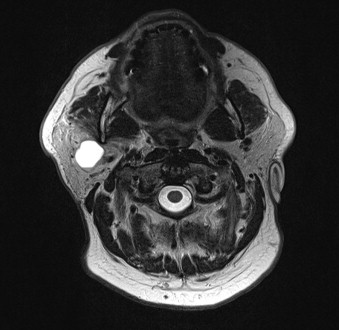

- The great majority of these tumors are located in the lower pole of the parotid gland:

- Tail of the parotid.

- These tumors are well encapsulated lesions with cystic and solid areas:

- These tumors consist of an oncocytic epithelial cell component arranged in double layers:

- Which develops cysts and papillary projections, and a variable amount of lymphoid tissue often with germinal centers: